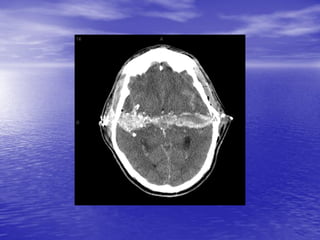

This document discusses the management of intracranial pressure and cerebral edema in neurocritical care patients. It covers topics such as how patients typically present with brain injuries, important caveats in neurological examinations, principles of cerebral resuscitation, mechanisms of primary and secondary brain injury, the pathophysiology over time, imaging techniques including CT scans and MRI, monitoring techniques like intracranial pressure monitoring, and treatment approaches like the use of hyperosmolar therapy with mannitol or hypertonic saline. The goal is to prevent secondary brain injury after the initial primary injury occurs.